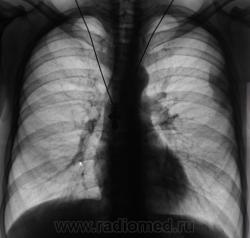

Ваше мнение уважаемые коллеги?  Пациент направлен на рентгенографию ОГК.

Навскидку хотел писать банальное осумкование но теперь сомнения.

Да, у меня тоже сложилось смутное впечатление, что "это" осумкование. Правда, сделали томограммы.

Нет, не банально.

Где ровные контуры? При чем тут волнистость? Почему как бы верхний край "надорван"? Почему нижний край плавно (без углов) переходит в костальную плевру?

В первую очередь - думаем о мезотелиоме, во второй - об осумковании...

Да, подорвали Вы мою уверенность Виктор Григорьевич. И контур полицикличный, да местами и не четкий, да, и не ровный. Действительно, а вдруг мезотелиома?